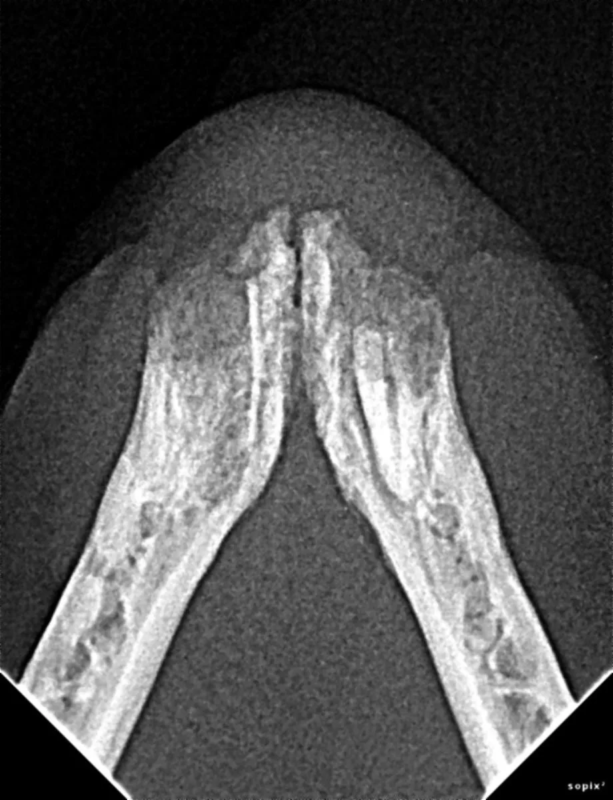

The Center now provides advanced imaging via cone beam CT. Cone beam CT is excellent for visualization of bony structures of the skull, nasal cavity, teeth, and ears. Cone beam CT is especially helpful for diagnosing dental disease and evaluation of jaw fractures. It can also be useful for evaluating the sinuses and tympanic bulla. Cone beam CT can be used in conjunction with nasal biopsy and culture to evaluate nasal discharge whether chronic or acute.

Periodontal disease is extremely common in dogs and cats. Over 80% of dogs and cats over two years of age have some degree of periodontal disease. Periodontal disease is best prevented by yearly professional dental cleanings starting at two years of age and at home brushing at least three times weekly. Brushing should begin at a very early age to allow your new pet to get used to regular brushing. In severe cases of infection or periodontal disease, the teeth may need to be surgically extracted. Extractions should always involve x-rays of the tooth first, as many teeth have multiple roots or may be diseased below where the eye can see. Extracting larger teeth in animals requires oral surgery, equivalent to removing wisdom teeth in people. It is vital that all of the tooth and roots be removed for the periodontal infection to resolve. In cases of important teeth with mild to moderate periodontal disease, multiple periodontal treatments can be offered to help save these teeth.

Pets can be involved in trauma that can cause fractures to their head, teeth, and jaw bones. Correctly repairing these fractures is extremely important for your pet to have normal function of their mouth. If a jaw fracture is allowed to heal in an abnormal position, your pet may have great difficulty chewing and can be in significant pain. Many fractures can be successfully treated with minimally invasive oral procedures, but more complicated cases may require bone plating techniques. The Center offers cone beam CT imaging which provides extremely detailed images of the bones of the head and skull. Advanced imaging with CBCT facilitates selection of the best surgical technique to get your pet back to eating and comfort as soon as possible.